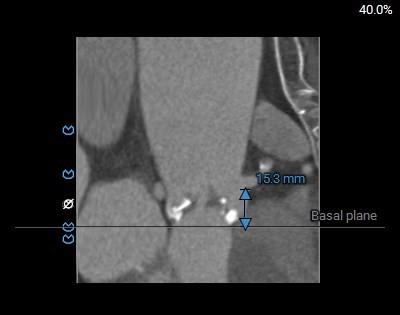

左室大小及冠脉阻挡风险

◇ 主动脉瓣环水平夹角52°,非横位心,主动脉弓角度较锐(43°)及弓距偏短;